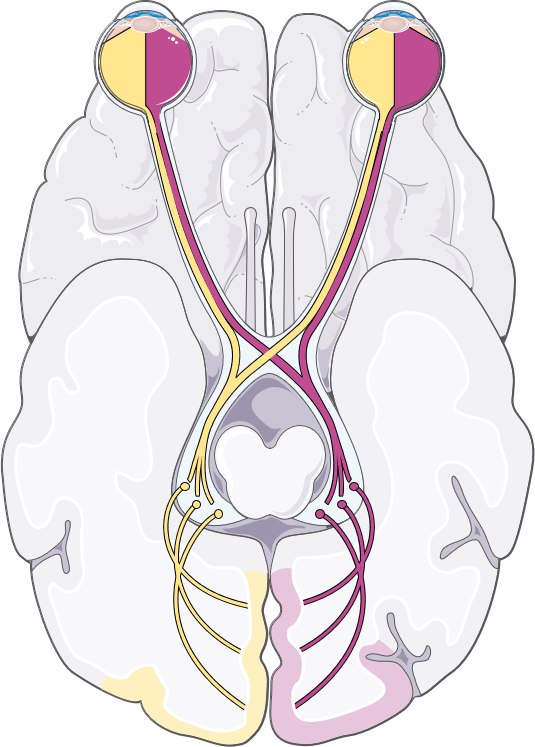

Секрет — в анатомии зрительных путей. Они частично перекрещиваются в области хиазмы, а затем идут в затылочную долю мозга — именно там формируется зрительное восприятие.

Если инсульт поражает правую затылочную кору, пациент теряет левые поля зрения обоих глаз — это называется гомонимная гемианопсия.

Если поражена левая затылочная доля, исчезают правые поля зрения. Это и есть правило зрительного перекреста.